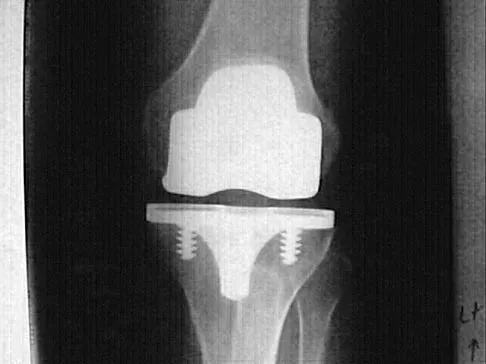

Figures 4a through 4c show the clinical photographs and radiographs of a 12-month-old boy who has progressive difficulty wearing shoes because of the length of the second toe, as well as width of the forefoot. Management should consist of

The patient has macrodactyly involving the second ray, with significant enlargement of the width and height of the foot. The radiographs show widening of the interval between the first and second metatarsal and between the second and third metatarsal. With this degree of involvement, amputation of the second ray with excision of the overgrowth of affected soft tissue provides the most consistent desired reduction in foot size. A threaded Steinmann pin should be inserted across the remaining metatarsals until healing has occurred. Patients with macrodactyly should be examined to exclude neurofibromatosis type 1 and Klippel-Trenaunay-Weber syndrome.